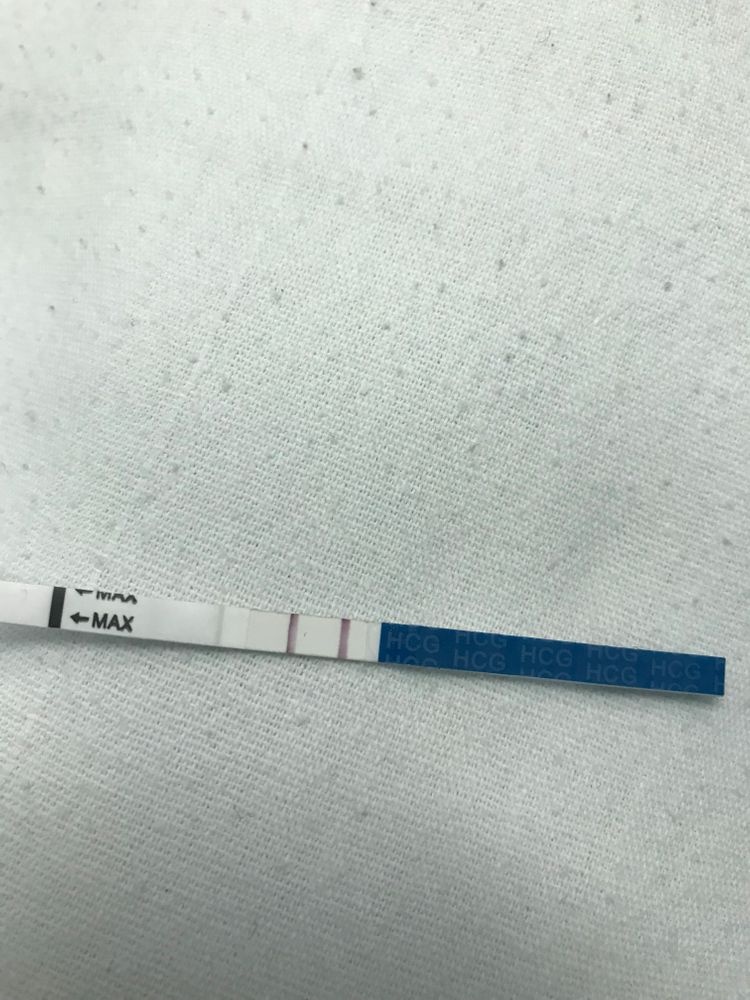

Наша жк желает лучшего… второй день колют мне кровоостанавливающее, попаверин и дают праджисан. Сегодня после обеда кровь перестала мазать. В чем моя проблема собственно…сейчас выходные и здесь только дежурные врачи, каждый раз новый. Последний сказал, что на хгч они анализ вообще не берут, а узи контрольное сделаем через неделю. Через неделю!!! Я в шоке. Как так? А если выкидыш был? А если замершая??? И мне неделю так лежать? Не знаю что даже делать. Попросила родных принести тесты на беременность… но информативны ли они? Как быстро падает хгч, про потере беременности? Как только принесли тесты, так сразу и сделала…не терпела чтобы какое-то время не мочиться и тд…тест мама чек. Так вот, что посоветуете делать? Очень надеюсь, что беременность сохранилась🙏